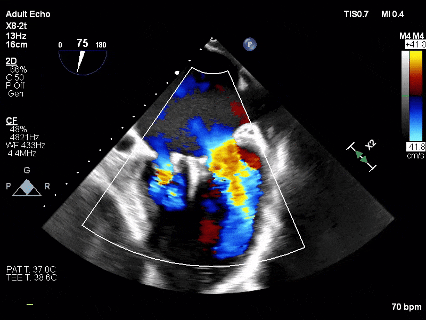

MR反流病因:DMR(部分腱索断裂)、Carpentier II型;

反流程度:极重度(5+),PISA法估测EROA约1.12cm²,R-VOL约98ml;

病变情况:P2-部分P3,脱垂宽度约27mm ,连枷间距11-13mm,瓣口面积7.8cm²,PML约25mm

其他:TR(重度) ,间接估测PASP约65mmHg;

预估手术难点:后叶冗长,脱垂宽度大,连枷间距大。

术前Bi-com

四条肺静脉均可测及收缩期反向血流

术前即刻TEE进一步明确了二尖瓣反流的机制(DMR)及反流程度(5+),重点完善了病变区域二尖瓣解剖结构的评估,预估手术难点/影响手术效果的解剖结构为冗长的二尖瓣后叶(PML约25mm),宽大的脱垂(Flail Width约30mm),超大的连枷间距(Flail gap约14mm)。